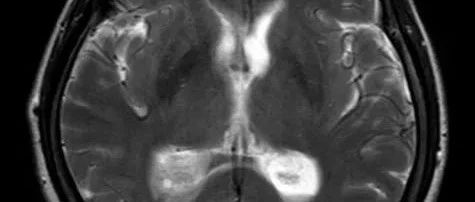

脑脓肿(brain abscess)是目前临床上较为严重的颅内化脓性感染疾病,感染途径有相邻感染病灶的传染、血行传播、隐源性感染及手术或颅脑外伤导致,其中隐源性 、血源性感染脑脓肿目前在整体脑脓肿的所占比例较高。脑脓肿以幕上多见,好发于皮质交界区,颞叶居多,其次是额、顶、枕叶,小脑半球和垂体囊肿少见,临床表现为全身感染症状和颅内压升高症状。病理脑脓肿的形成分为四个阶段:(1)脑炎早期:3~5 天,局灶性炎症,...

77岁免疫健全男性,表现为进行性头痛和意识模糊。MRI可见大量脓肿。脑脊液化验提示白细胞计数为1250个/mm3(中性粒细胞占65%),微生物培养阴性。二次脑活检,行通用PCR提示为梭杆菌属。最终诊断:脑脓肿。